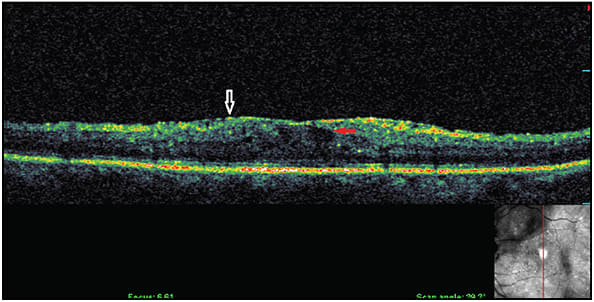

In the presence of VMT or ERM, it is important to isolate the main driver of DME. Is it a tractional element or vascular element (which can be confirmed using FA)? In cases of a vascular element as the main driver (Figure 5), intravitreal steroids can be tried in pseudophakic patients or FA-guided focal laser can be applied to the leaking microaneurysms. However, bear in mind that using continuous wave (CW) laser photocoagulation may increase traction, and subthreshold diode micropulse (SDM) laser may be safer.

Figure 5. DME presenting with cysts (red arrow) and vitreomacular abnormality (white arrow), which might not be involved in DME pathology.